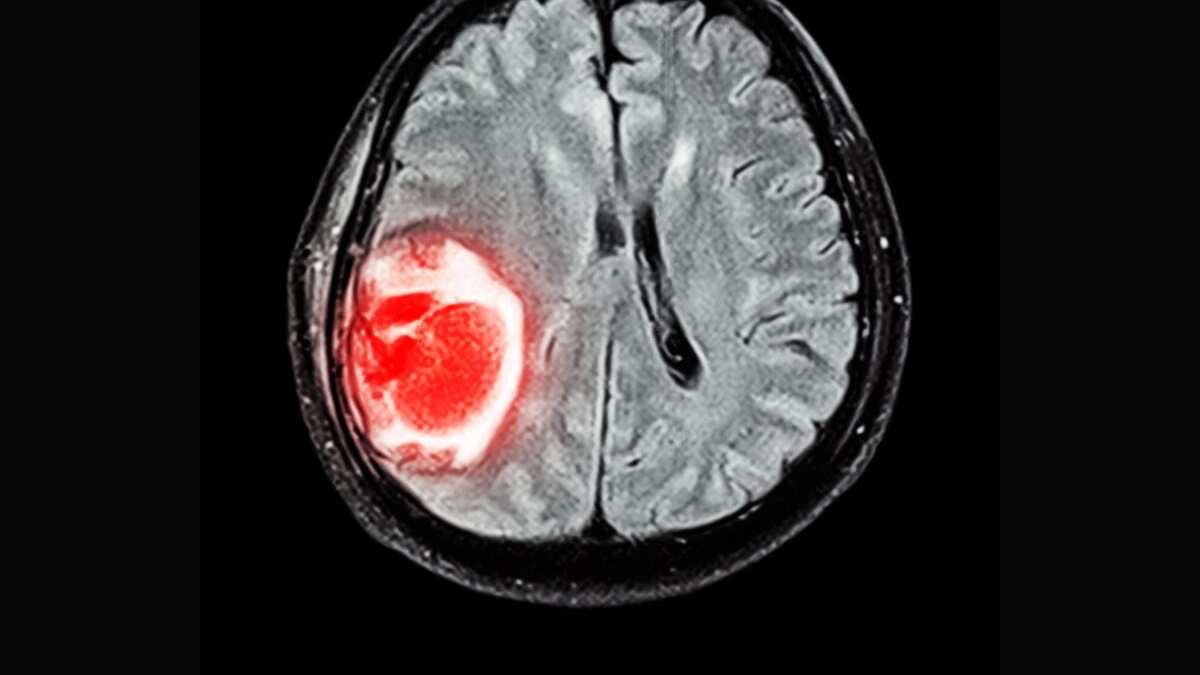

Según Mayo Clinic, el síndrome de Guillain-Barré es un trastorno poco común en el cual el sistema inmunitario del cuerpo ataca los nervios, generalmente resultando en una parálisis irreversible.